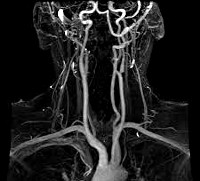

МРТ сосудов. Современная методика диагностики, основанная на эффекте ядерного магнитного резонанса. Во время процедуры устройство считывает электромагнитные волны, полученные путем колебания ядер атомов водорода, после чего компьютер преобразует полученную информацию в трехмерное изображение тестируемой зоны. МРТ сосудов позволяет обследовать артерии, вены и лимфатические сосуды любого места, чтобы провести детальную оценку состояния сосудистых сетей, выявить патологические изменения на ранних стадиях и определить причину развития патологии. Используется в онкологии, неврологии, сосудистой хирургии, ревматологии, кардиологии и других областях медицины.

Сосудистая МРТ также позволяет создавать трехмерные изображения, увеличивать отдельные части этих изображений, изменять угол зрения и изучать различные участки. Преимущество данной методики заключается в более широких возможностях воспроизведения изображения исследуемой области в различных плоскостях. Кроме того, во время МРТ сосуды, ткани и анатомические структуры одинаковой плотности более четко различаются, что позволяет более точно оценить степень тяжести и распространенность патологических изменений.

МРТ сосудов головного мозга позволяет создавать детальные трехмерные изображения сосудистых сетей и окружающей мозговой ткани, выявлять гематомы, кровоизлияния, аневризмы, артериовенозные фистулы и зоны нарушений кровообращения. МРТ показывает кровеносные сосуды в случаях подозрения на посттравматическую внутричерепную гематому, инсульт, хроническую церебральную ишемию, энцефалопатию, посттравматические или постинсультные изменения, а также при вегето-сосудистой дистонии, аденоме гипофиза, болезни Паркинсона и других патологических состояниях. Тест может быть как родным, так и контрастным.